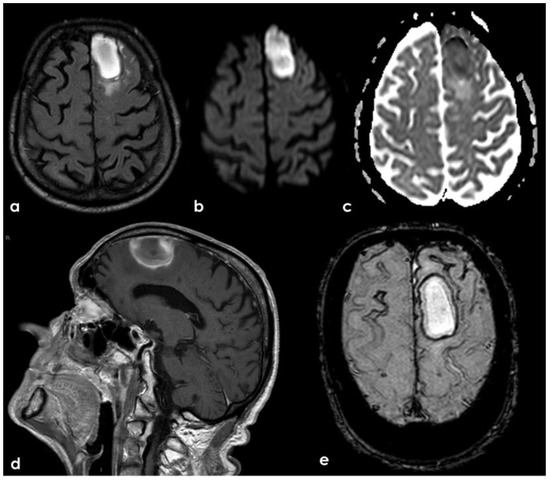

2. December 2013: Sulcal SAH and TFNEs